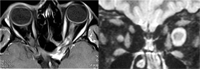

- Neuritis óptica anterior / papilitis

Se presenta con pérdida visual, defecto pupilar aferente y dolor periorbitario que aumenta con los movimientos oculares asociado a edema de papila. El estudio se dirige a las enfermedades desmielinizantes, principal etiología de las neuritis. La prueba de imagen de elección es la RM craneal y orbitaria con finalidad diagnóstica, pronóstica (mayor riesgo de desarrollar esclerosis múltiple si aparecen lesiones características), y evolutiva (el realce de las lesiones con contraste sugiere enfermedad en fase aguda). Las secuencias FLAIR son las más adecuadas para mostrar las lesiones desmielinizantes (Figura 4). La RM orbitaria puede obviarse en casos muy típicos de neuritis con lesiones desmielinizantes en la RM craneal.

Figura 4. Izquierda: edema de papila en neuritis óptica típica. Centro: lesiones desmielinizantes en RM craneal (T2). Derecha: engrosamiento del nervio óptico izquierdo en RM orbitaria (T1)

En los casos atípicos sigue estando indicada una RM craneal y orbitaria, asociando otras pruebas complementarias según la sospecha diagnóstica (serologías, marcadores de autoinmunidad, punción lumbar, etc.). Las secuencias T1 con supresión grasa son las más adecuadas para apreciar el realce en la porción orbitaria del nervio óptico. La RM espinal se indica por la sospecha de neuromielitis óptica: episodios recurrentes de neuritis óptica anterior o retrobulbar con menor recuperación visual de lo esperado, asociados o no a mielitis transversa, y cuya RM craneal no es compatible con esclerosis múltiple (EM) (Figura 5).